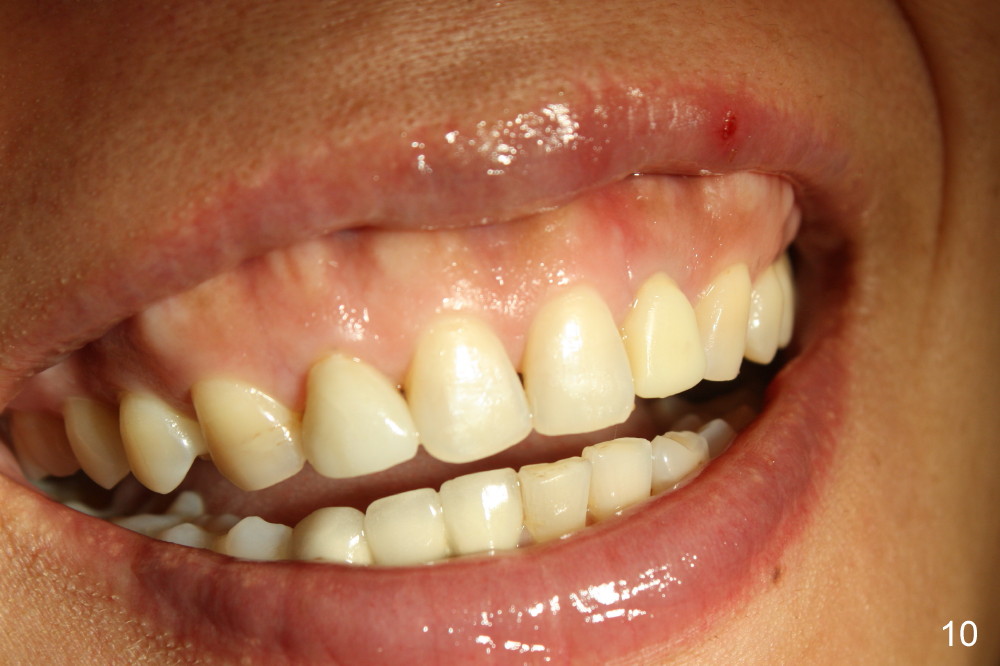

The gingival architecture around the immediate provisional is normal 5 months postop (Fig.10,12). To increase cosmetics for the definitive restoration, the abutment length is reduced (compare arrowheads in Fig.11 to 12).